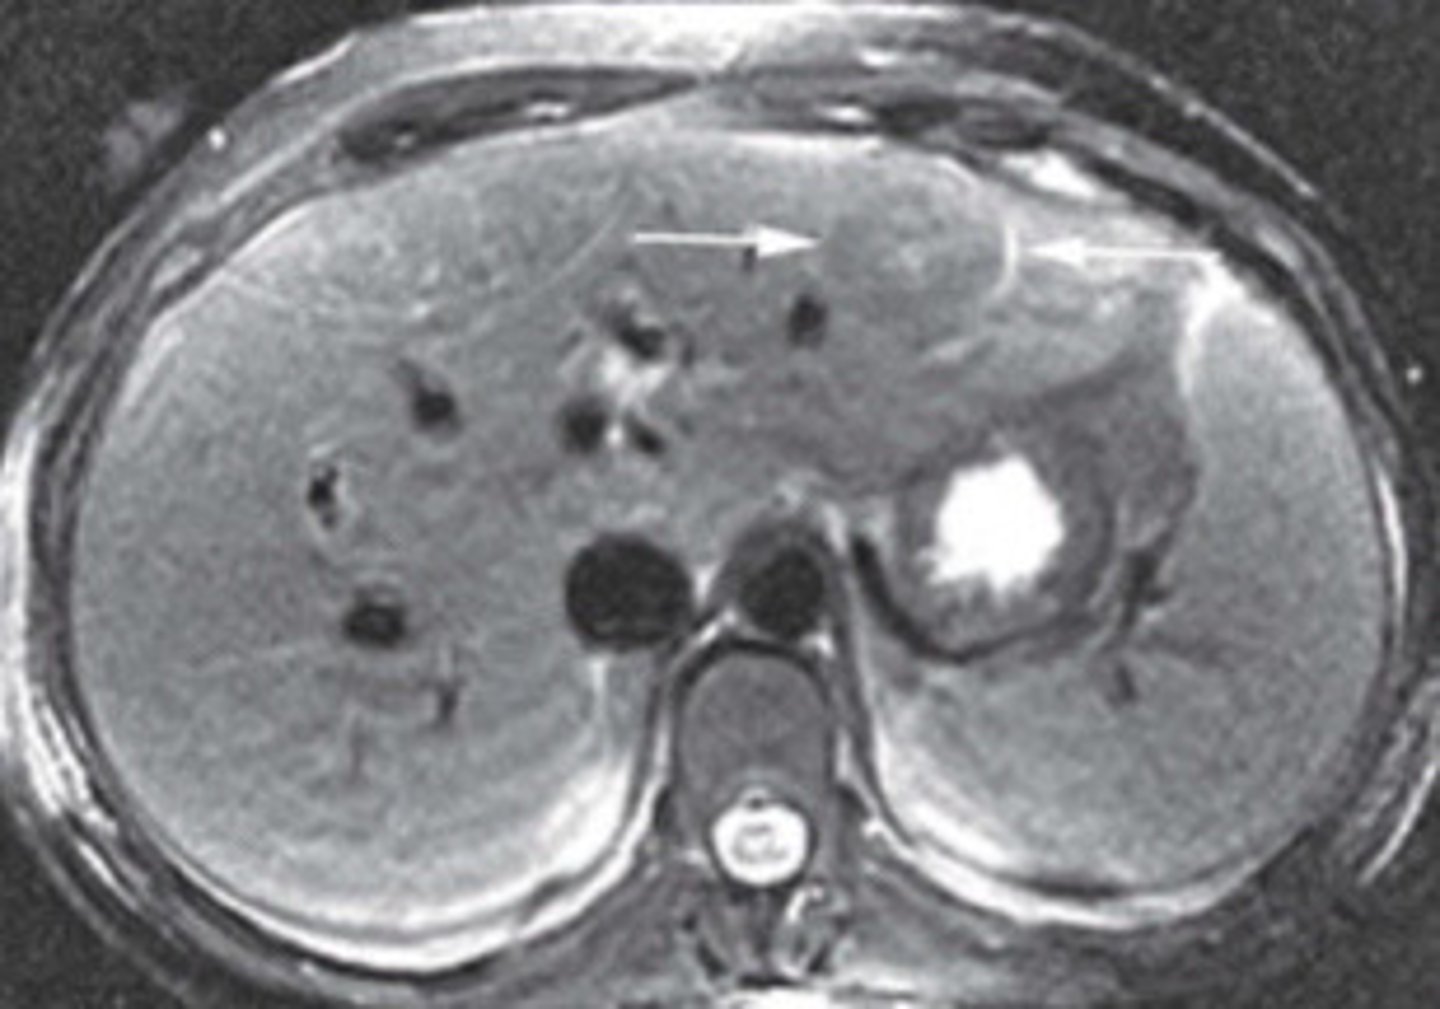

Adenoma

What does this image show